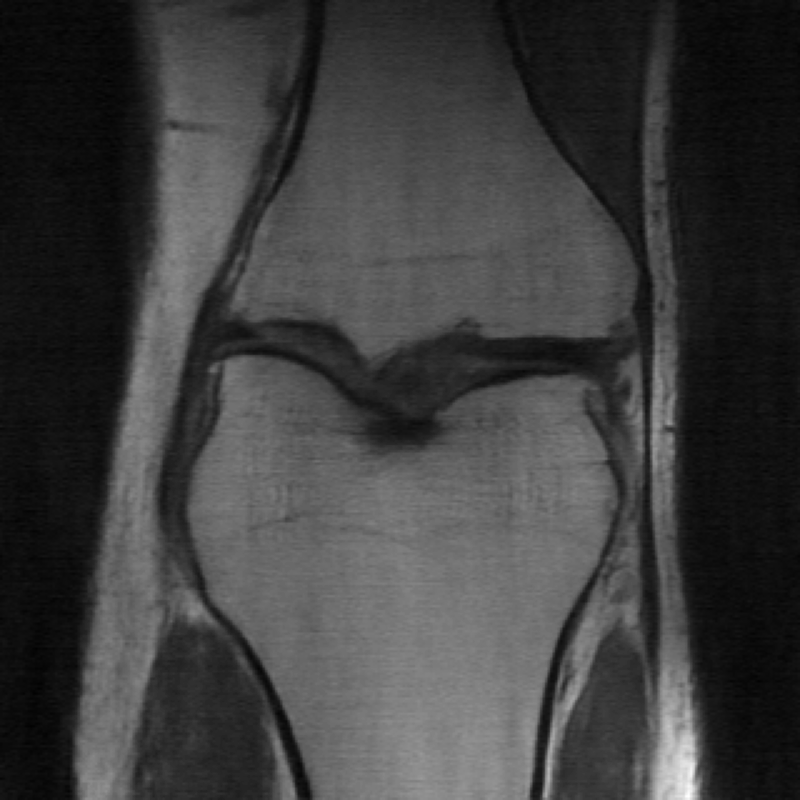

The data used in the undersampled MRI experiments were obtained from the NYU fastMRI Initiative [45]. The primary goal of the fastMRI dataset is to test whether machine learning can aid in the reconstruction of medical images. We trained and tested on a subset of the single-coil knee dataset, which consist of simulated single-coil measurements. In all tests, we use complex-valued data, which interfaces with our deep networks by treating the real and imaginary parts of the images as separate channels. We measure reconstruction accuracy with respect to the center 320320 pixels of the complex IFFT of the fully-sampled k-space data. For the purpose of visualization, we display only the magnitude images in the following sections.

In Table 1 we present our main results. We present sample reconstructions for the deblurring problem and MRI reconstruction problem in Figs. 7 and 8. For reference, the ground truth, inputs to the networks, a total variation regularized reconstruction, and a RED reconstruction are presented in Figs. 5 and 6. We also provide in the Appendix a table of SSIM values as well as the full version of Table 1, which contains the standard deviations of PSNR.

While the magnitude of the improvements vary across domains and problems, we find that retraining the network with the proposed model adaptation techniques significantly improve performance by several dBs in the new setting. This effect is particularly striking in the case of MRI reconstruction with MoDL, where the βnaiveβ approach of replacing with in the network gives catastrophic results (a roughly 9 dB drop in reconstruction PSNR), while the proposed model adaptation approaches give reconstruction PSNRs within 1-2 dB of the baseline approach of training and testing with the same forward model in the case where is known.